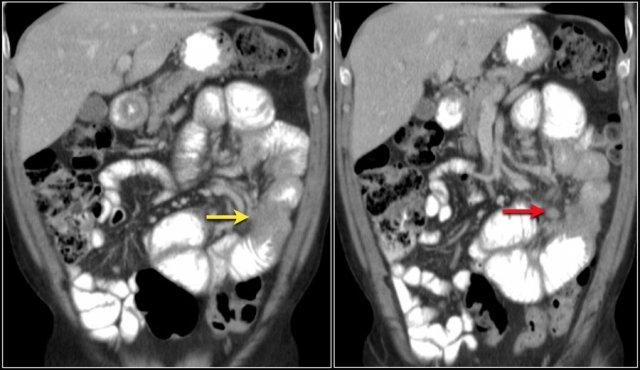

Các hình ảnh cho thấy một khối hình vòng ngắn gây tắc nghẽn ở hỗng tràng (mũi tên vàng) kèm hạch bạch huyết to (mũi tên đỏ).

Kết quả giải phẫu bệnh xác nhận là ung thư biểu mô tuyến.

Chuỗi xung T1W sau tiêm thuốc tương phản từ có fat-sat (trái) và chuỗi xung T2W (phải) cho thấy một khối gây tắc nghẽn ở hỗng tràng với bờ dạng vai (mũi tên).

Có giãn ruột trước chỗ hẹp.